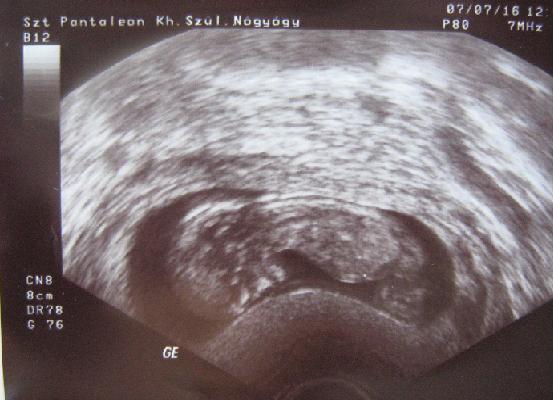

És végre a kép (ha sikerül feltöltenem :? ) :)

Kép

Ekkor volt 54 mm-es az ülőmagassága. :)